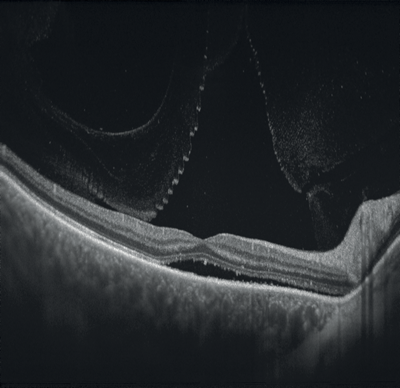

Figures 1-4: Swept-source OCT (DRI OCT-1 Triton, Topcon) images of healthy eyes that clearly delineate features in the vitreous, including area of Martegiani, bursa premacularis and posterior hyaloid, right through to the sclera, in the same single scan.

Figures 8 and 9: Case examples from clinical sites: choroidal neovascularisation associated with AMD visualised using fluorescein angiography and optical coherence tomography angiography (images courtesy of Optovue, Inc, CA, USA).